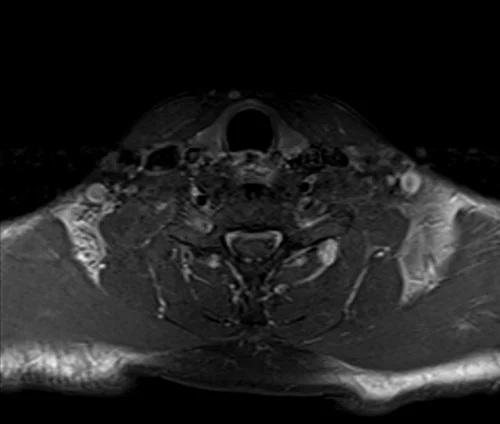

SI JOINTS